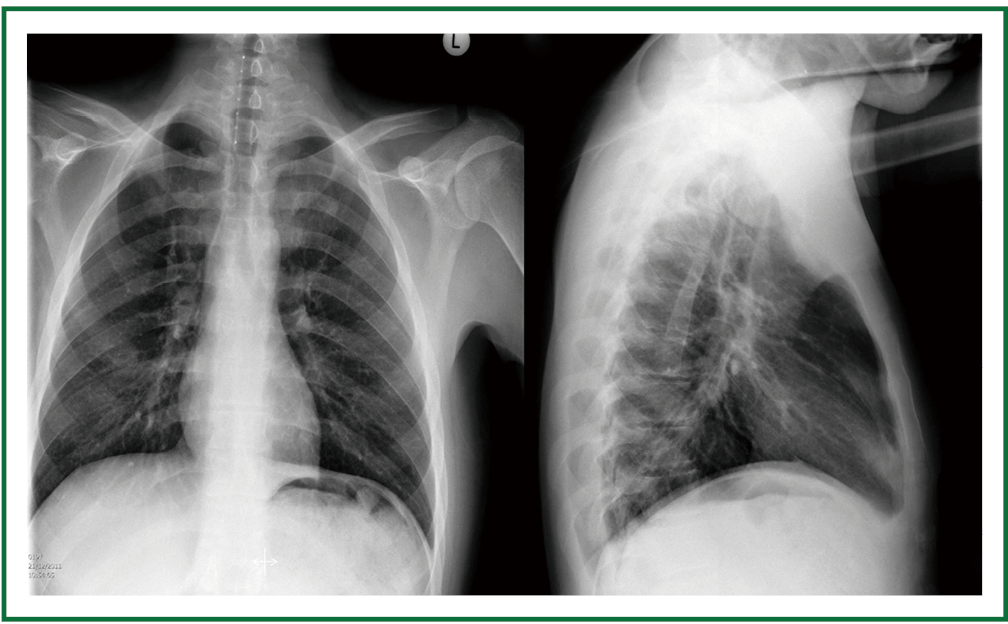

Tracheostomy Tube X Ray Chest X Ray Showed The Standard Tracheostomy Tube In The Correct

The tip of the tracheostomy tube should be half way between the stoma and the carina at the level of the d3 vertebra. Evaluation of endotracheal tube position.